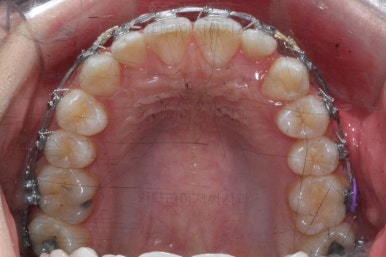

왜소치 좌우로 틈을 일부러 만든 상태입니다.

그 후에 임시 개념으로 사이즈를 크게 만들어 줬어요.

사이즈를 크게 한 뒤에도 약간의 틈이 남아서 다시 틈을 줄여주는 과정을 진행했어요.